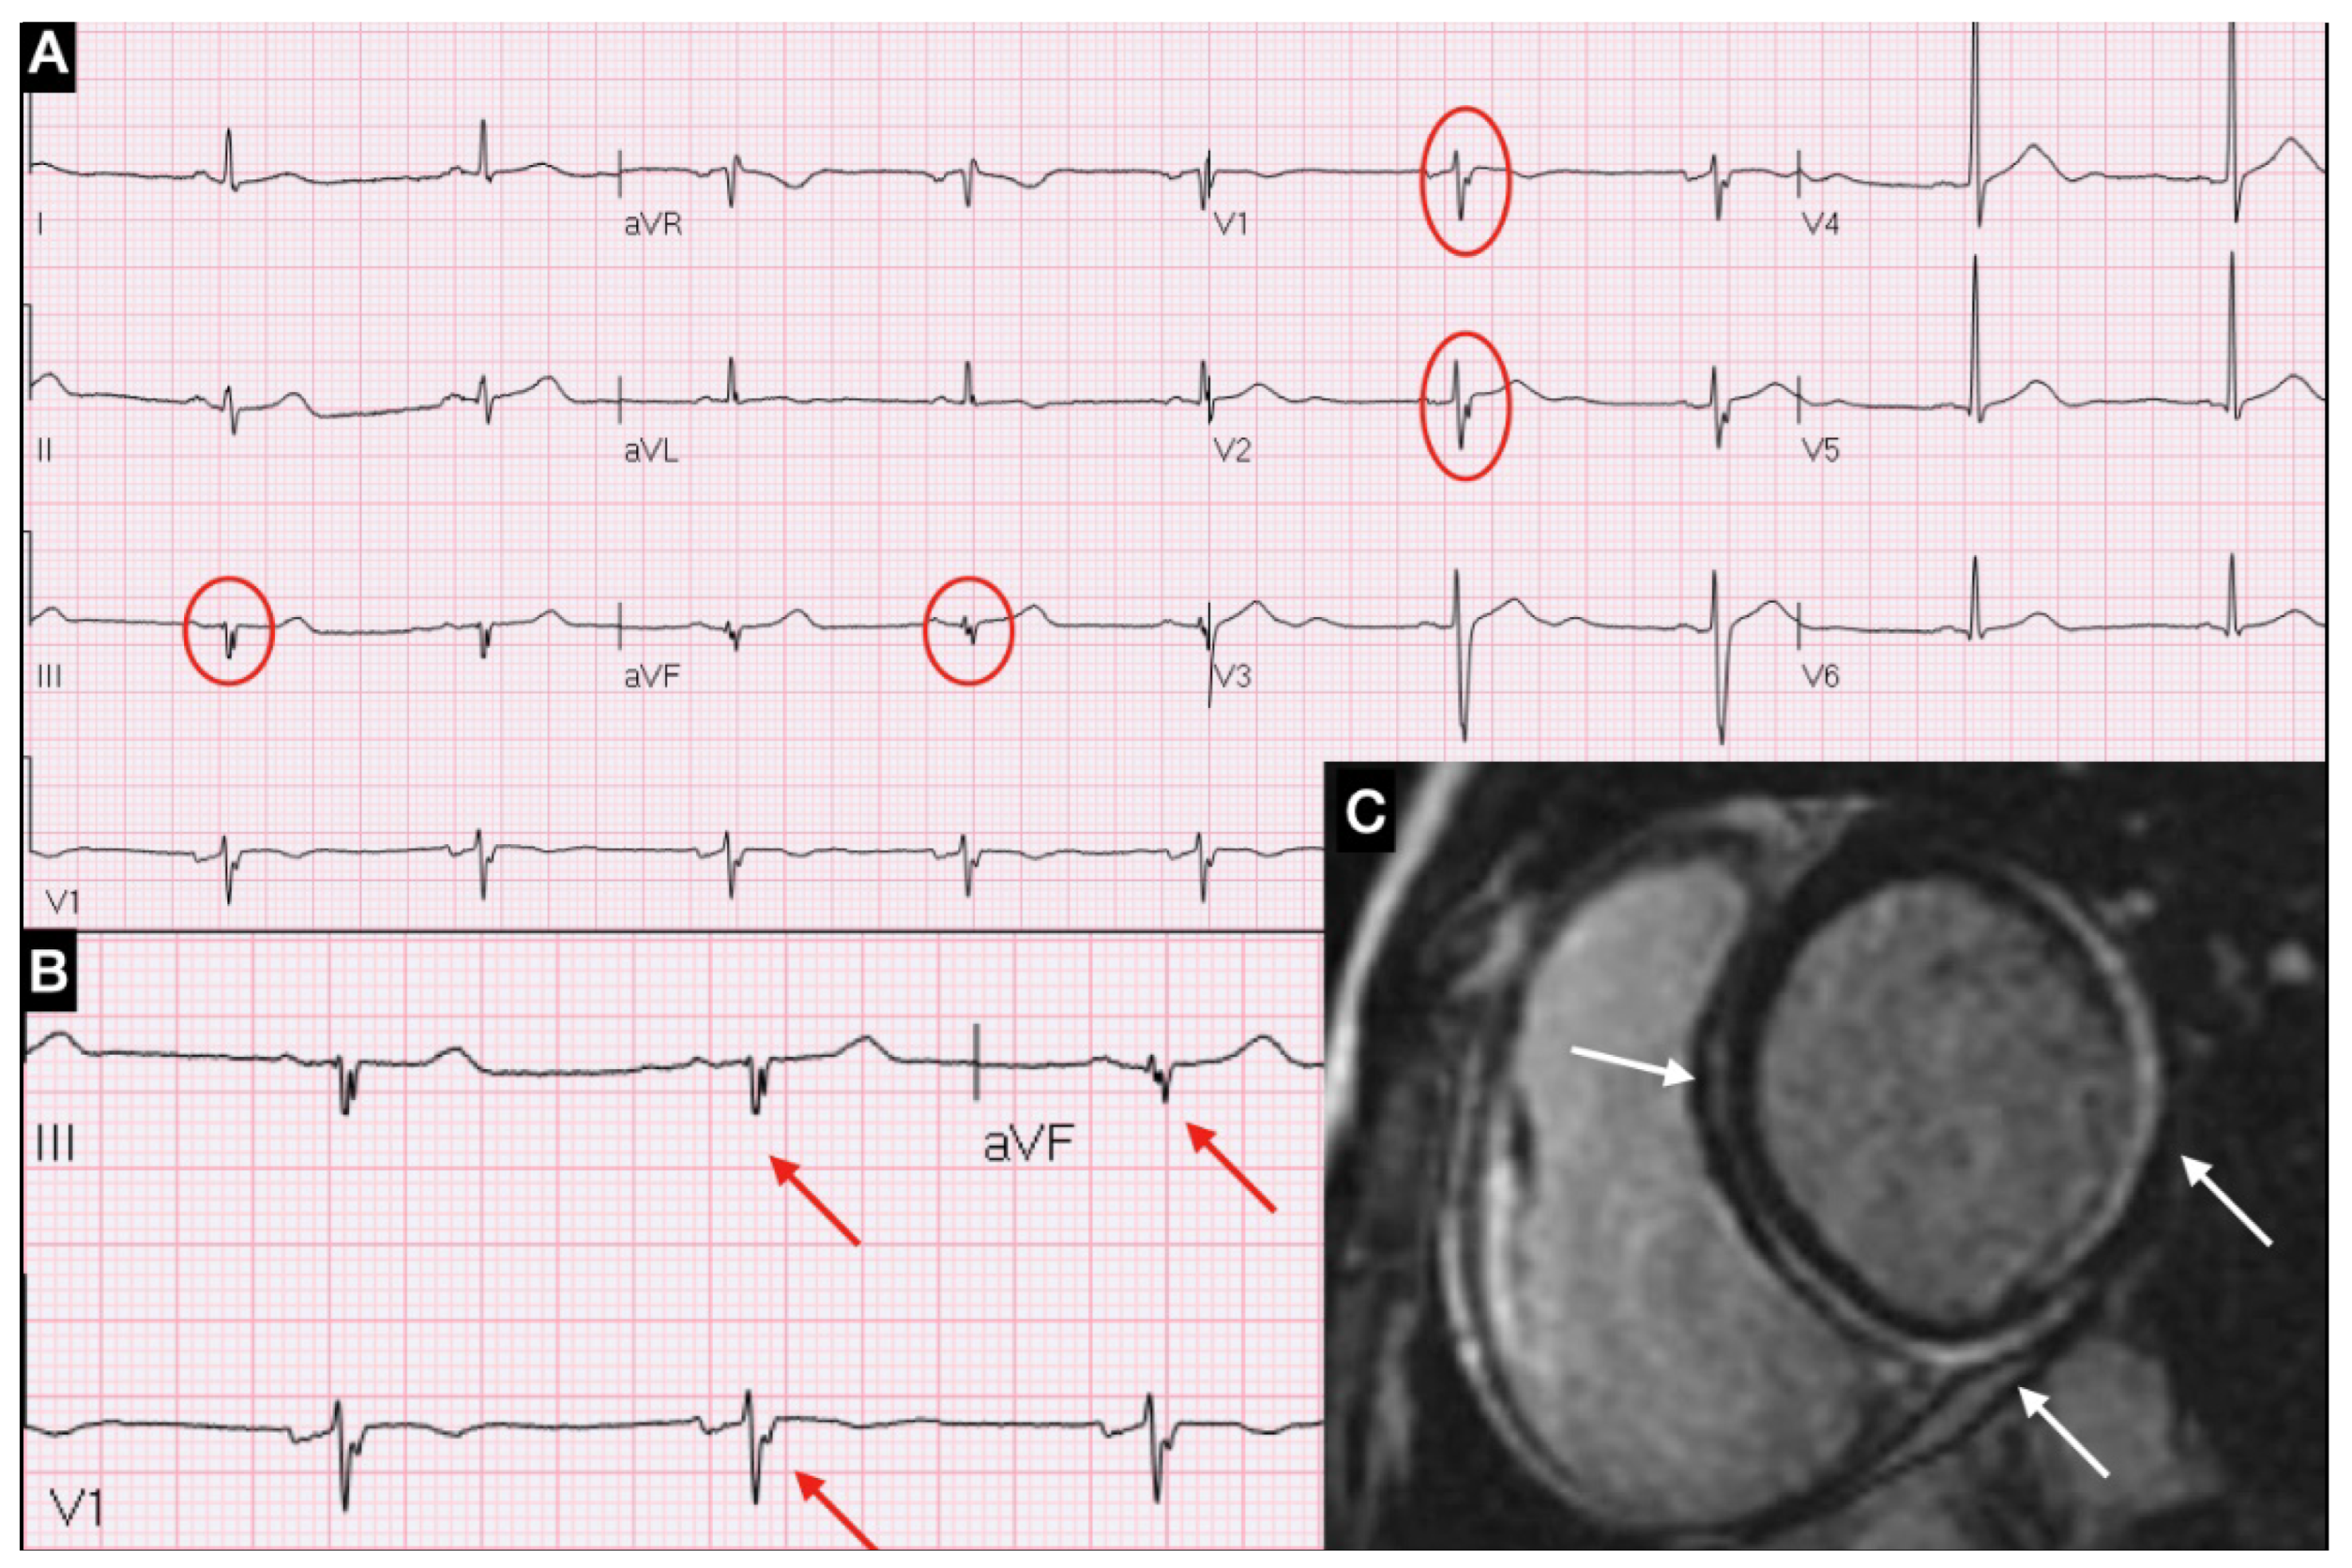

In this study, we observed that systematic search of fQRS in the first ECG recorded in the ED may be useful for the early triage of patients with suspected myocarditis (Figure 2).

Figure 2. Algorithm assessment of patient with suspected myocarditis in Emergency Department.

It has previously shown that the presence of QRS fragmentation is associated with evidence of LGE at CMR and impairment of contractility [29,30]. Based on this background, we can hypothesize that the early recognition of myocardial inflammation indicated by presence and extension of fQRS might identify a subset of higher-risk patients, which may deserve early specific work-up (Figure 2). In our cohort, fQRS initially correctly classified 40 out of 51 patients in which acute myocarditis was eventually ascertained. Interestingly, QRS fragmentation appeared with a latency of a few days after symptoms onset. This is consistent with the time elapsed before a critical threshold of inflammation is reached in order to be detected on surface ECG.